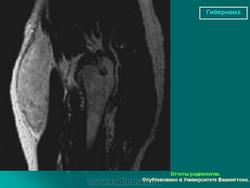

Гибернома (син.: бурая липома, липома из липобластов, мультилокулярная липома) — редкая доброкачественная опухоль, гистогенетически связанная с элементами бурого жира.

Гиберномы локализуются в определенных местах — на спине (в межлопаточной области), на боковой поверхности шеи. в подмышечных ямках, паховых областях, подколенных ямках. Их локализация совпадает с местом расположения бурого жира. Возраст больных чаще молодой — до 30 лет. Пол значения не имеет.

Гибернома (hibernus - зимний) - редкая форма опухоли жировой ткани.По внешнему виду напоминает бурый жир животных, впадающих в зимнюю спячку. Встречается как доброкачественный, так и морфологически злокачественный вариант опухоли с характерной локализацией в межмышечных прослойках подмышечной области, шеи, межлопаточной области. Может локализоваться в средостении, редко на конечностях. Возникает у людей молодого или среднего возраста. Клинические симптомы те же, что и при липомах. Имеет характерные гистологические отличия от липомы, но во многом и сходна по строению с ней.

Гибернома (hibernus - зимний) - редкая форма опухоли жировой ткани.По внешнему виду напоминает бурый жир животных, впадающих в зимнюю спячку. Встречается как доброкачественный, так и морфологически злокачественный вариант опухоли с характерной локализацией в межмышечных прослойках подмышечной области, шеи, межлопаточной области.

Может локализоваться в средостении, редко на конечностях. Возникает у людей молодого или среднего возраста. Клинические симптомы те же, что и при липомах. Имеет характерные гистологические отличия от липомы, но во многом и сходна по строению с ней.